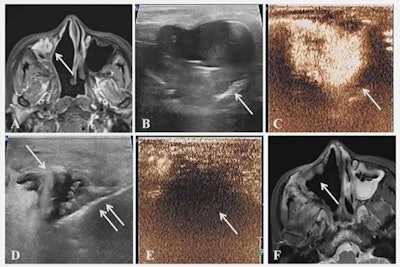

A case presented at the ARRS annual meeting shows the results of successful microwave ablation (MWA) treatment for a 39-year-old female with metastatic fibrosarcoma of the right axillary sinus.

Jiang also presented some case reports, including one case that described where a 39-year-old was treated for metastatic fibrosarcoma of the right maxillary sinus. Images taken 12 months after MWA showed that the tumor had disappeared.